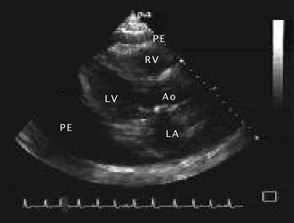

Ecocardiografice

clivare de spatiu pericardic sau spatiu transsonic (lichid) de diverse grosimi si localizari;

ingrosare de pericard cu eventuale depozite de fibrina (uneori libere in lichid).

Semne ecocardiografice:

lichid pericardic in cantitate mare (evidentiaza si dispunerea topografica a acestuia),

colaps AD, VD (protodiastolic) si AS,

EcoCG in tamponada cardiaca